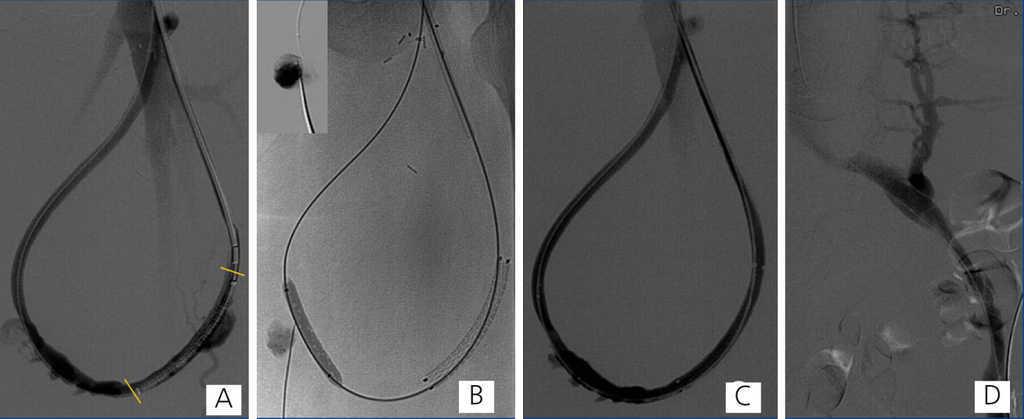

Here we present the case of a 46-year-old patient with chronic renal failure, on trimestral haemodialysis for 23 years secondary to obstructive uropathy, with a left femoral loop (21 months of use) with occluded iliac venous drainage that produced oedema in the leg and three pseudoaneurysms in the therapeutic range. One of these was actively bleeding. The three pseudoaneurysms and occlusion of the left primitive iliac vein were treated using endovascular methods under local anaesthesia. The actively bleeding pseudoaneurysm was excluded with a covered stent, and the other two were percutaneously embolised using balloon-assisted thrombin injections in order to avoid thrombosis in the prosthesis. The iliac venous axis was recanalised and treated with angioplasty balloons; in the final angiographic controls, we observed no pseudoaneurysms, with patency of the prosthesis, iliac venous drainage, no signs of collateral circulation, and without having produced any complications.

Figure 2. Stent, fluoroscopic images, and fistulography